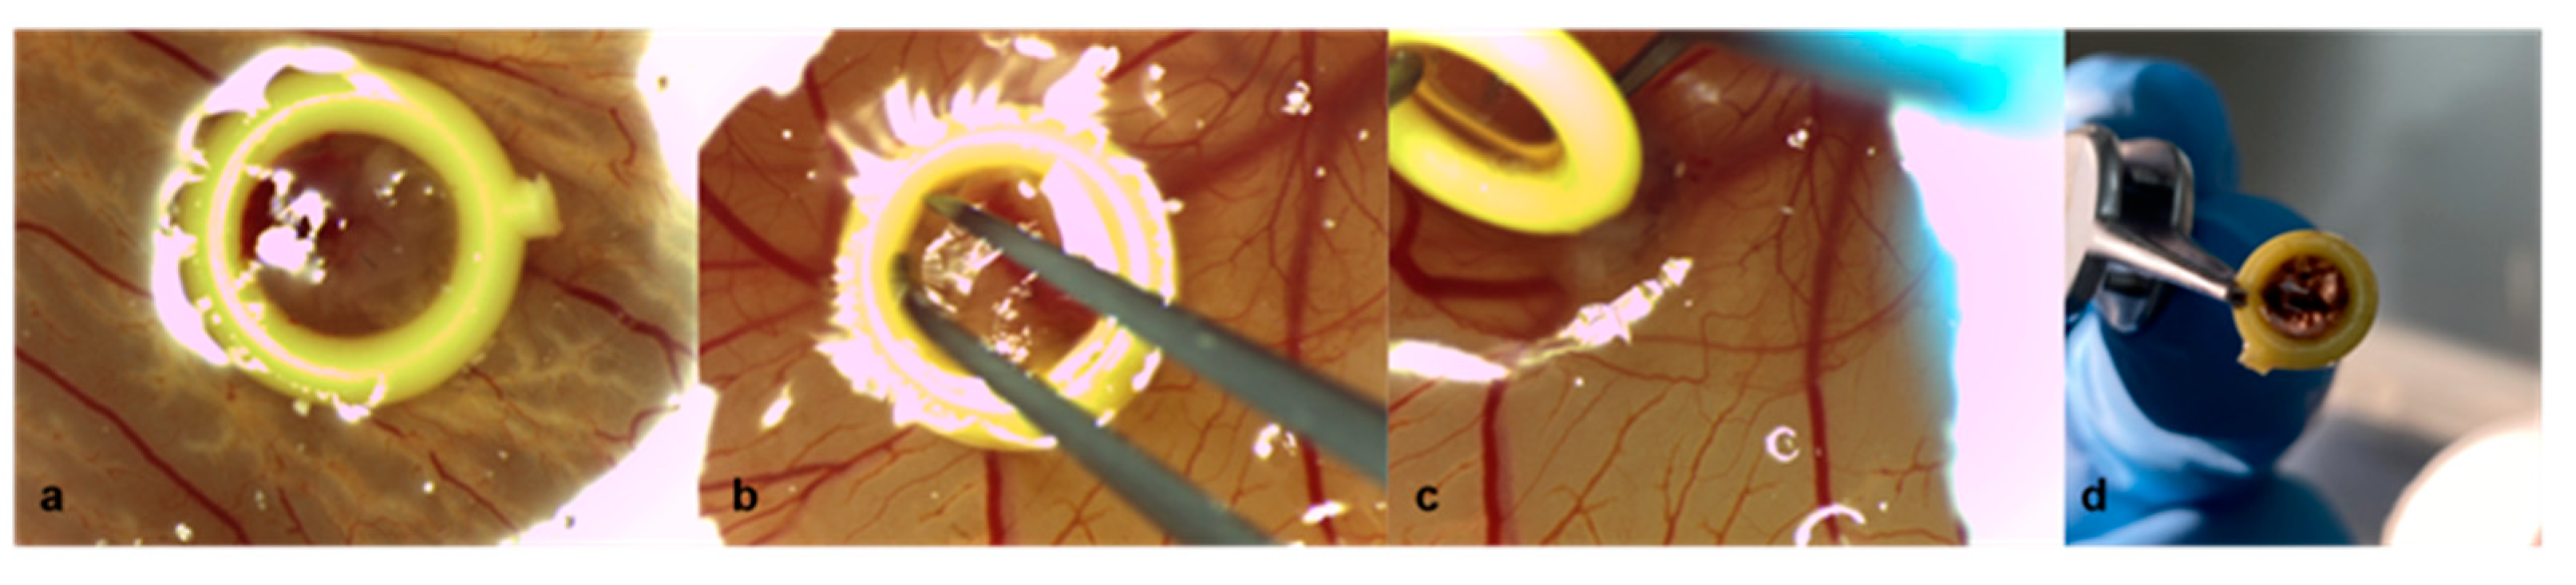

2.1. Chicken Chorioallantoic Membrane Assay

2.2. Patient-Derived Xenografts

2.3. Characterization of Tumor Grafts

3.1. Characterization of Tumor Grafts